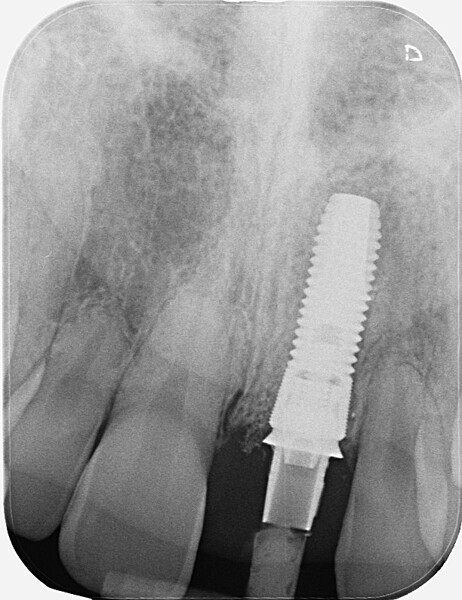

Fig. 1: Single-tooth exposure of tooth #21 after recurrent marginal gingivitis. Owing to the initial diagnosis of extensive resorption, the tooth could not be preserved.